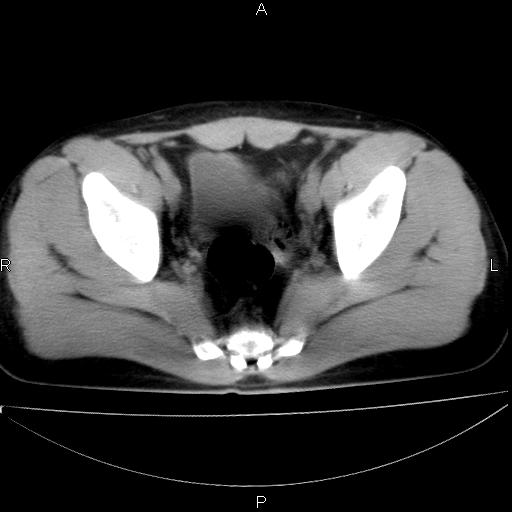

标题: CT29462:双测输尿管扩张

男 25岁 自述 尿频尿急,排尿困难20多天.无腰痛, b超说左肾盂轻度积水,左输尿管上端扩张.未见结石影. ct我看双侧肾盂轻度积水,双输尿管上端都扩张,大家看看能看见结石吗?

双肾轻度积水,双侧输尿管上段扩张(原因待查)。

双输尿管扩张下端未见高密度结石和输尿管晕轮征,不好说是结石.增强后如何?

双肾盂及双输尿上段轻度积水,双输尿管未见明显结石影。